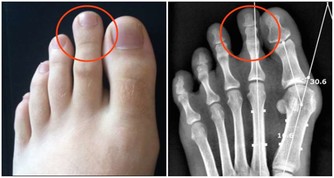

3.脫髮嚴重、指甲脫落、皮膚乾燥等問題。